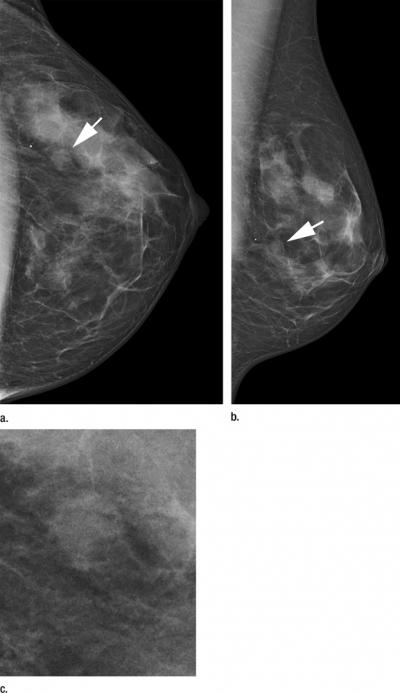

The DR photon-counting scan system had a cancer detection rate of 0.76 percent for subsequent screening, compared with 0.59 percent for the other screening units. The recall rate was 5.4 percent for the photon-counting method and 3.4 percent for the other methods.

"The higher cancer detection resulting from the use of the DR photon-counting scan system is due to high detection of both small, invasive cancers and ductal carcinoma in situ," Dr. Heindel said.

The photon-counting technique had almost twice the detection rate of other methods for ductal carcinoma in situ (DCIS), an early, noninvasive form of disease. It had a higher DCIS detection rate than the statewide units and the conventional DR subgroup.